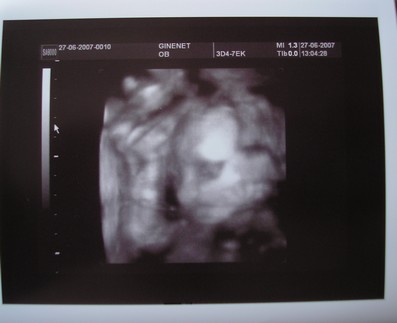

Lányok, én olyan boldog vagyok először is, minden renbden van velük, mindenük szép és oké, éééééés, az egyik babám tutira fiú, mert láttuk a herezacsikat, a másik pedig képzeljétek, olyan faramucin feküdt, hogy nem mutatta meg magát, a doki szerint lány, de ez nem tuti....hát, én nagyon örülök, és még a könnyem is kicsordult, annyira szerettem volna fiú gyereket

teljesült a szülinapi kívánságom,